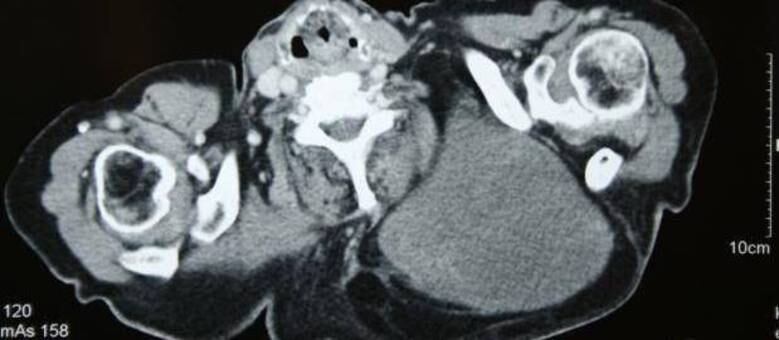

Os exames realizados em sua cidade revelaram a presença de um tumor do tipo lipossarcoma, que nasce nas células de gorduras mais profundas. No caso dessa paciente, informou o instituto, se tratava de um lipossarcoma gigante de retroperitônio, que estava localizado entre o peritônio parietal e os músculos que ficam na parede abdominal posterior.